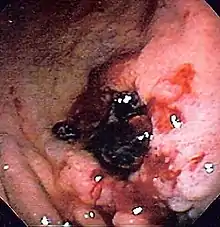

| Endoscopic image of a posterior wall duodenal ulcer with a clean base, a common cause of upper gastrointestinal bleeding. | |